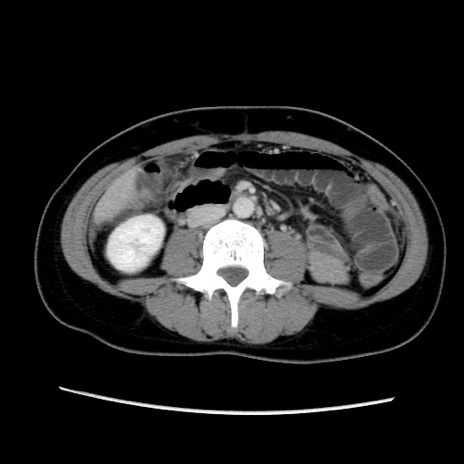

症例39(横断像)

【症例】40歳代女性

【主訴】上下腹部痛

【現病歴】2日目から下腹部痛あり。夜間は痛みで眠れなかった。昨日より上腹部痛と下痢が出現。臥位で痛みは軽快したため、休んでいた。本日になって臥位でも立位でも痛みが強くなってきたため救急要請。

【既往歴】子宮内膜症

【身体所見】部:平坦・軟、左上下腹部に圧痛あり、反跳痛あり。

【データ】WBC 21800、CRP 26.78